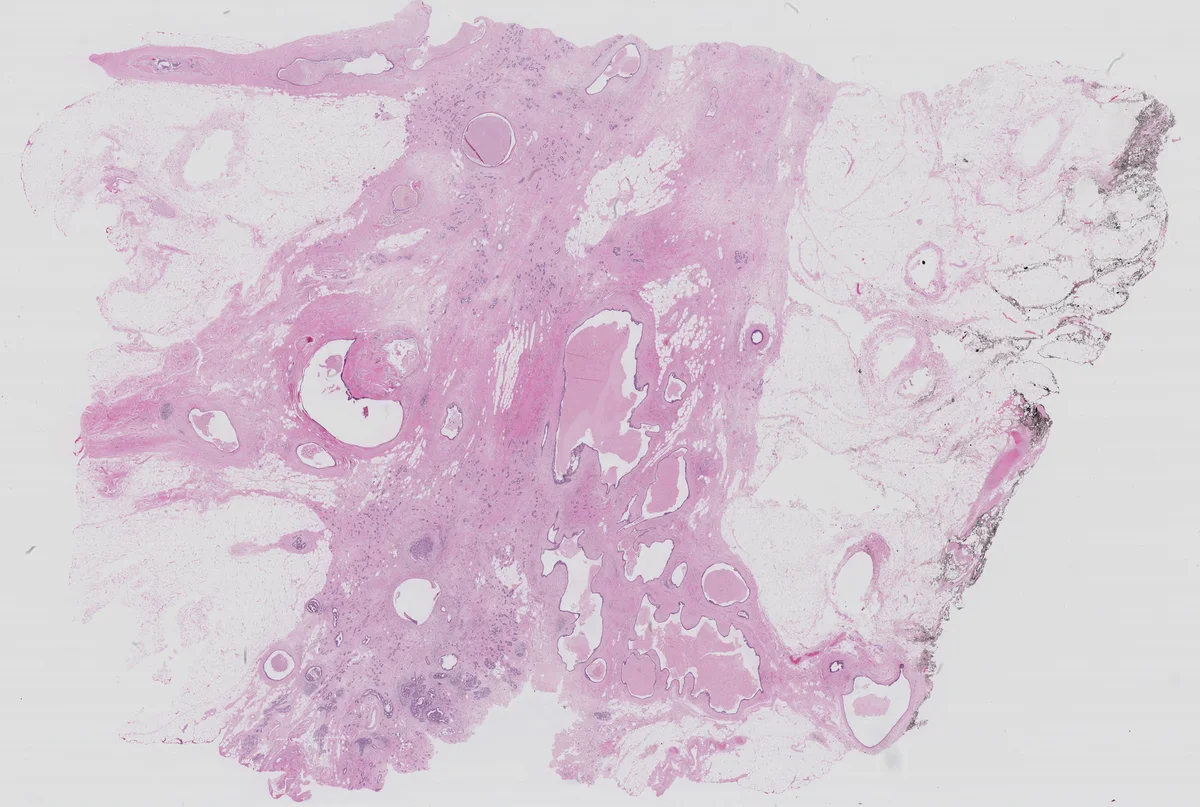

본 논문은 슬라이딩 윈도우 기반 전체 슬라이드 이미지(WSI) 분할 시 전역 컨텍스트가 부족한 문제를 해결하기 위해, 고해상도 슬라이스와 저해상도 전체 이미지를 동시에 입력으로 받는 이중 입력 구조와 주의(attention) 기반 특징 융합 모듈을 제안한다. 제안된 DA‑RefineNet은 기존 단일 입력 모델에 비해 평균 IoU, 정확도, 전용 Score 모두에서 향상된 성능을 보이며, 특히 경계 영역에서의 일관성을 크게 개선한다.

손실 함수는 픽셀‑레벨 교차 엔트로피와 함께 클래스 불균형을 보정하기 위한 가중치를 적용했으며, 평가 지표는 평균 IoU(MIoU), 전체 정확도(Accuracy), 그리고 논문에서 정의한 전용 Score를 사용하였다. ICIAR2018 데이터셋(400장의 유방 조직 슬라이드)으로 5‑fold 교차 검증을 수행했으며, 기존 U‑Net, RefineNet, 그리고 최신 멀티‑스케일 방법들과 비교했을 때, 전역 정보를 보강한 DA‑RefineNet은 평균 MIoU 78.3% (U‑Net 71.2% 대비)와 Score 0.84 (U‑Net 0.77 대비)를 달성했다. 특히 경계 부근에서 발생하는 라벨 불일치를 크게 감소시켜, 임상 전문가가 기대하는 전반적인 일관성을 제공한다.